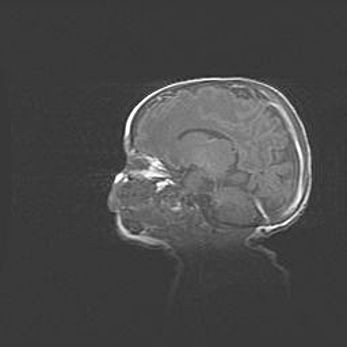

Аномалия Денди-Уокера. Признаки гипоплазии мозолистого тела.

Возраст: 5 месяцев 3 дня

Вес: 5550 г

Пол: мужской

Окружность головы: 39 см

Срок гестации: 40 недель

Аномалия Денди-Уокера – это порок развития головного мозга, для которого характерна триада симптомов: гипотрофия или аплазия червя мозжечка и/или полушарий мозжечка, расширение четвёртого желудочка с формированием ликворной кисты задней черепной ямки, гипертензионная гидроцефалия различной степени.

Гипоплазия мозолистого тела относится к дефектам внутриутробного этапа развития мозговой ткани, возникающим в процессе закладки структур головного мозга, что происходит на начальных этапах развития эмбриона.